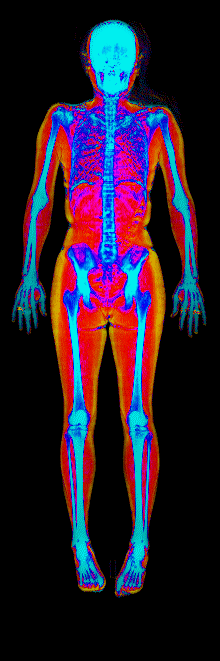

This page features real, anonymized DEXA scan images from BodyStats clients, organized by gender and body fat percentage in 5% increments. DEXA (Dual-Energy X-ray Absorptiometry) is the clinical gold standard for measuring body composition — far more accurate than scales, calipers, or visual estimates.

Each colorized scan shows the distribution of fat tissue (shown in warmer colors) and lean tissue (cooler colors) throughout the body. Compare your own DEXA scan to others in your range, or see what different body fat levels actually look like on a scan.

Female DEXA Scans by Body Fat %

15 to 20% body fat